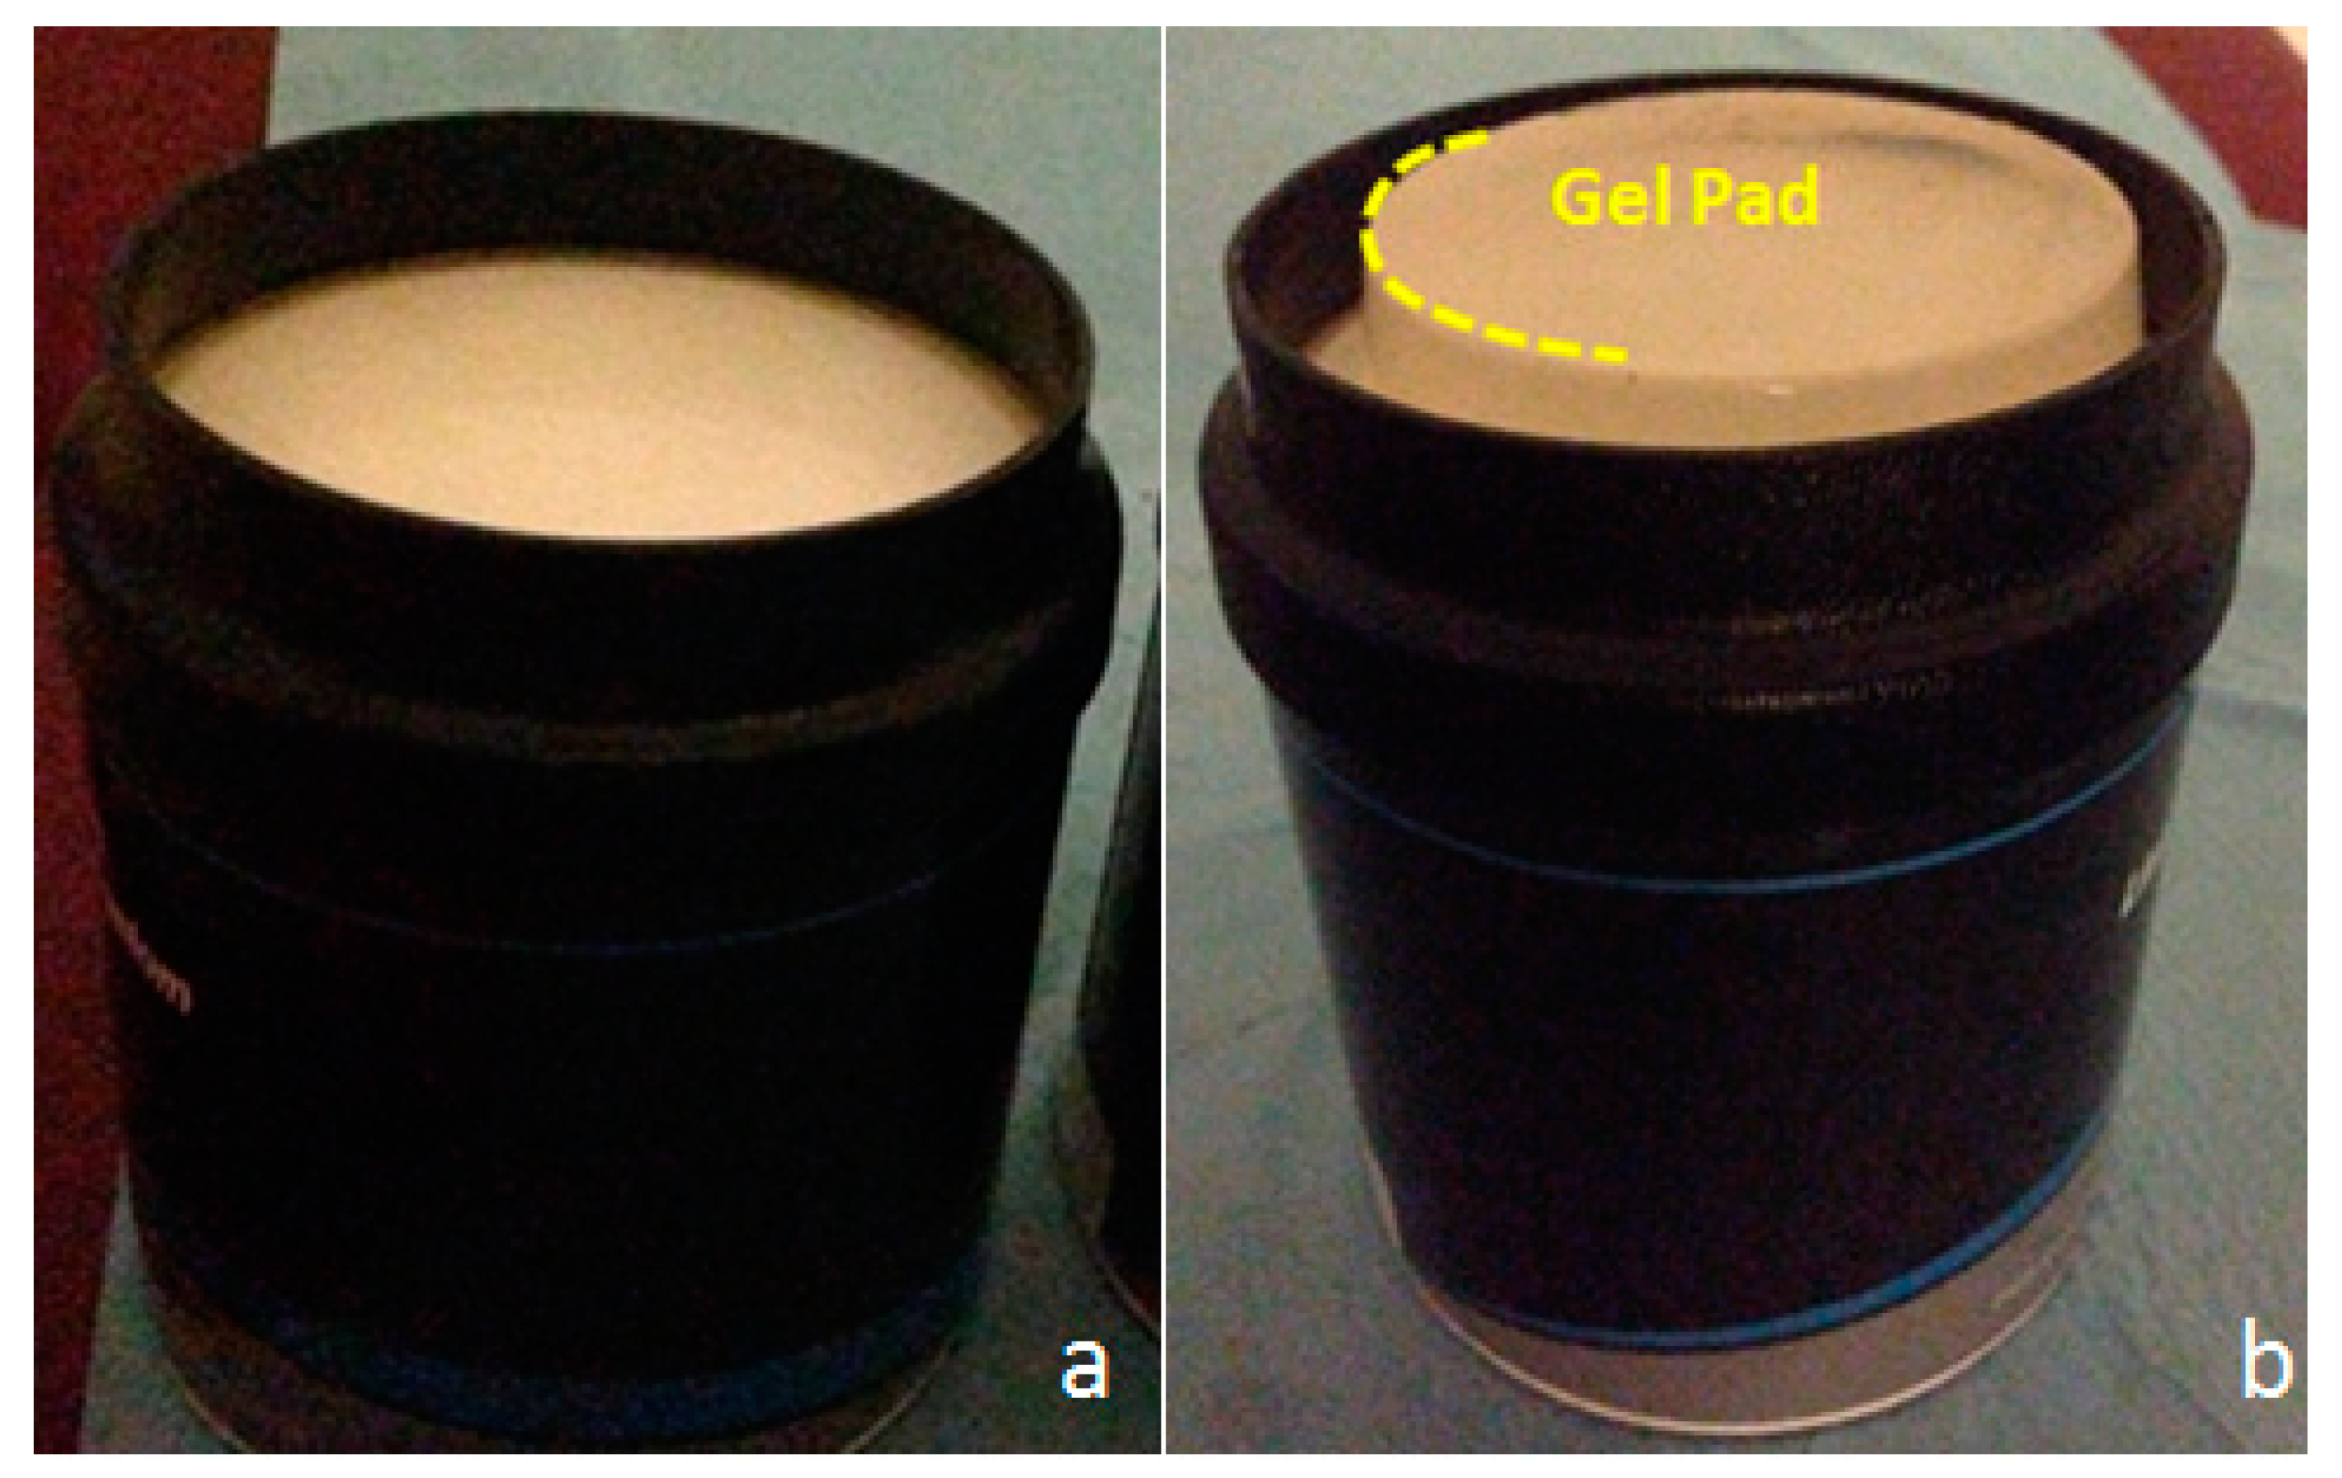

2.2. Ultrasonic-Based Elastography Phantoms